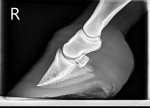

X-rays showed nothing too concerning, thankfully. No sinking, 6degrees rotation on bad foot and 4 on other, but given how sore she is, vet was very relieved and prognosis is good.